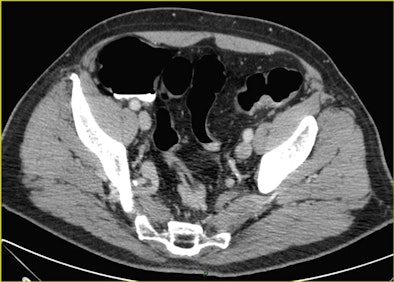

| A 70-year-old man underwent CTC after incomplete colonoscopy at the transverse colon showing a large stenotic lesion in the splenic flexure with bleeding and high-grade dysplasia. CT colonography revealed dolichocolon, a second stenotic lesion in the sigmoid colon, and a tumor in the left kidney, precluding a laparoscopic approach. All images courtesy of Dr. Riccardo Rizzeti. |